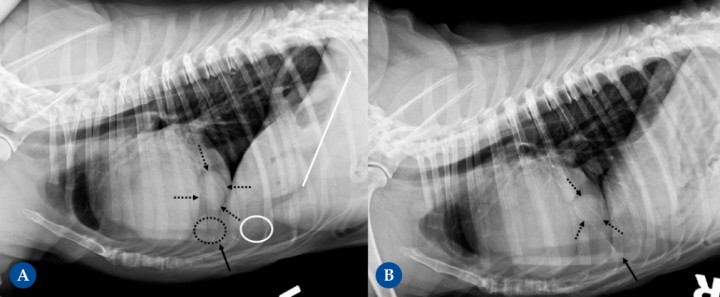

(A) Proyección lateral izquierda. (B) Proyección lateral derecha. Cruce de Labrador, hembra castrada, 9 años. Hernia peritoneo-pericárdico diafragmática conteniendo parte del hígado, vesícula biliar y grasa falciforme. Hallazgo incidental sin sintomatología asociada, se detecta como parte de protocolo diagnóstico neurológico por posibles convulsiones. Aspecto globoso de la silueta cardíaca que presenta un aumento moderado del tamaño, unos márgenes redondeados en las diferentes proyecciones ortogonales y un desplazamiento dorsal de la tráquea. Se observa signo de silueta entre el margen caudoventral de la silueta cardíaca y el diafragma (flecha negra). La silueta cardíaca presenta una opacidad mixta tejido blando y grasa, con la presencia de una área aproximadamente nodular de opacidad tejido en el margen caudal, ventral a la vena cava caudal en las proyecciones laterales (6ª espacio intercostal) (flechas negras punteadas). Además, se detecta presencia de contenido de opacidad grasa (círculo punteado). En el abdomen craneal incluido, se detecta una disminución evidente del tamaño de la silueta hepática (signo del abdomen vacío) [círculo blanco], sin visualizarse el aspecto ventral de los lóbulos hepáticos y con un desplazamiento craneodorsal marcado del eje gástrico (región pilórica) (la línea blanca representa el eje gástrico desplazado; debería ser paralelo a las costillas, perpendicular a la columna vertebral).